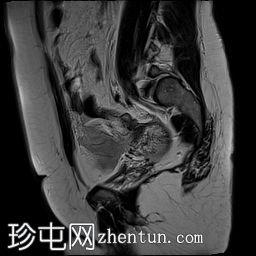

矢状位

T2加权像

可见子宫外腹腔内妊娠囊,内含胎儿组织。

该妊娠囊向后推移子宫,并与剖宫产瘢痕凹陷处紧密相连。

该妊娠囊与相关肠袢无法分离。可见其与性腺血管密不可分,且性腺血管明显突出。

胎盘位于妊娠囊后方,紧贴子宫前壁。

沿妊娠囊下缘可见一处异质性局灶性积液,最大轴向尺寸约为 8.4 × 5.5 cm,T1 加权像呈异质性高信号,T2 加权像呈异质性中等信号,T1 脂肪抑制序列未见信号下降,提示为血液成分。该积液压迫膀胱。

可见周围脂肪间隙呈条索状改变。

左侧卵巢无法辨认。

右侧卵巢未见实性或囊性肿块。

子宫体积增大,后倾,子宫内膜厚度约 1 cm,子宫下段前壁可见局灶性变薄(既往子宫瘢痕)。子宫连接区完整,未见肌层肿块。可见子宫内膜腔边缘有血性分泌物。